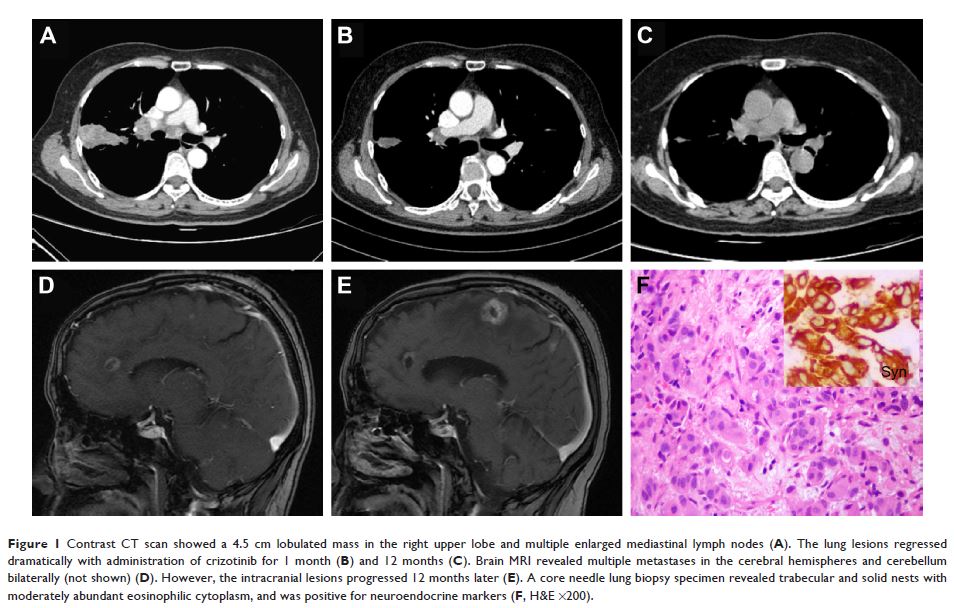

ALK -重排肺神经内分泌癌:对罕见病例系列和文献综述的综合研究